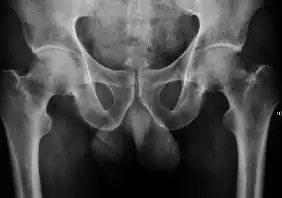

Plain radiography allows us to categorize the hip as normal or dysplastic or with impingement signs (pincer, cam, or a combination of both). Besides these, pathologic processes like osteoarthritis, inflammatory diseases, infection, or tumors can also be identified (Figure 1).[1]

Figure 1.

Radiography in normal hip

X-ray in pincer impingement type of hip dysplasia

X-ray of cam

Hip in osteoarthritis

Septic arthritis

In adults, one of the main indications for radiographs is the detection of osteoarthritic changes (Figure 1(e)). Nevertheless, radiographs usually detect advanced osteoarthritis that can be graded according to the Tönnis classifications. The grading system ranges from 0 to 3, where 0 shows no sign of osteoarthritis. Intermediate grade 1 shows mild sclerosis of the head and acetabulum, slight joint space narrowing, and marginal osteophyte lipping. Grade 2 presents with small cysts in the femoral head or acetabulum, moderate joint space narrowing, and moderate loss of sphericity of the femoral head. Grade 3 is the severest form of osteoarthritis, which manifests as severe narrowing of the joint space, large subchondral cyst with productive bone changes that may lead to deformity of the bone components of the joint, while secondary osteoarthritis due to calcium pyrophosphate deposition can be diagnosed when calcification of hyaline cartilage and fibrocartilage is detected.[1]

There are other pathological conditions that can affect the hip joint and radiographs help to make the appropriate diagnosis. Acute bacterial septic arthritis can be diagnosed by radiographs when a fast regional osteoporosis and destructive monoarticular process develops (Figure 1(f)). In case of tuberculous or brucella arthritis it is manifested as a slow progressive process, and diagnosis may be delayed.[1]